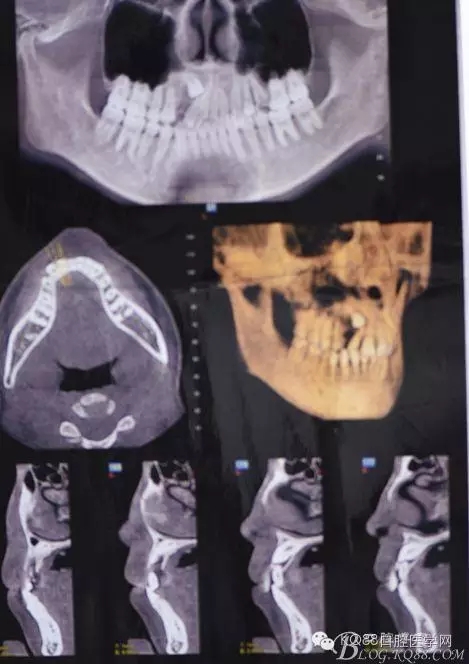

圖1.術前的cbct檢查:13位于12遠中根尖區(qū),13牙根接近上頜竇、53牙根滯留。